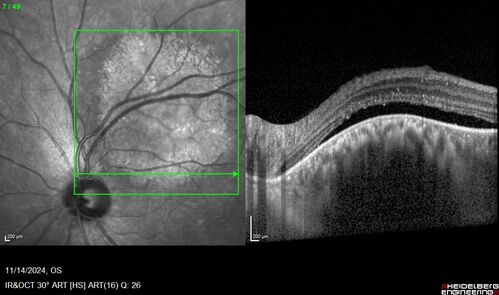

Small choroidal melanoma

28 year old man Serial images suggested that the lesion is growing

OD: sc20/16

OS: sc20/40+2

IOP: TP: OD:19 OS:16